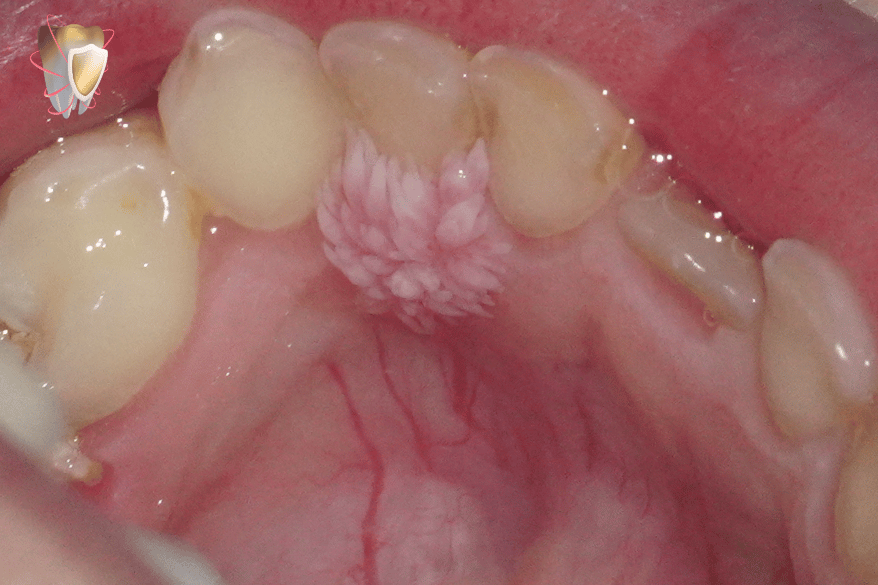

Squamous cell papilloma in 7 years old male patient :-

-irritating 2 white masses causing discomfort related to upper and lower arches.

-palatal gingiva related to upper deciduous lateral incisor.

– 2 fungating & cauliflower-like masses forming finger like projections .

Size: 0.9 cm X 0.5 cm. Upper

Origin: pedunculated.